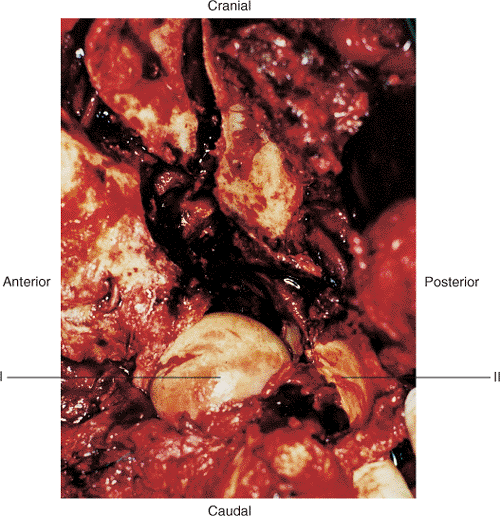

without damaging its neurovascular bundles (Fig. 43.1).

Figure 43.1. The extended iliofemoral approach for exposure of a comminuted left both-column acetabular fracture. (i) Femoral head. (ii) Abductor muscles and tensor fascia lata. (iii) Schanz pin in greater trochanter parallel with femoral neck.

(see Fig. 43.1).

capsule. If not present, exposure of the acetabular articular surface

facilitate visualization (Figs. 43.1 and 43.14).